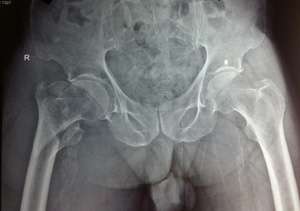

Figure 1a Varus reduction as demonstrated by medial overlap of fragments (thin arrow). Also note lateralization of entry point (thick arrow).

Figure 1b Manipulation with Steinmann pin to correct neck shaft angle as demonstrated by medial continuity and correction of overlap (arrow).